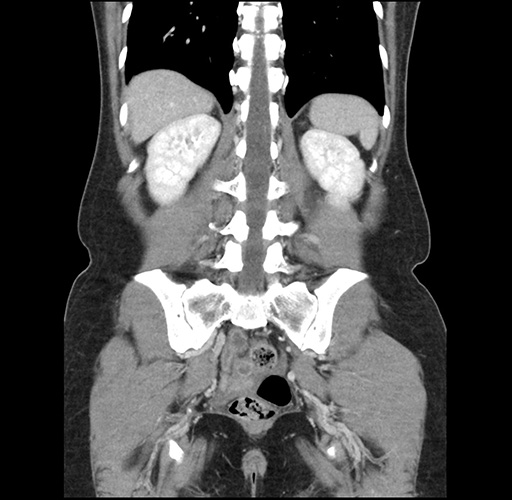

Imaging Analysis

Look through the patient's CT scan to identify any areas of concern for the necessary procedure.

Based on your CT findings, which issue(s) would give reason for "planned slowing down moment(s)" in this case?

Considering a standard left lateral sectionectomy procedure, what step(s) of the operation would you do differently in this case ?